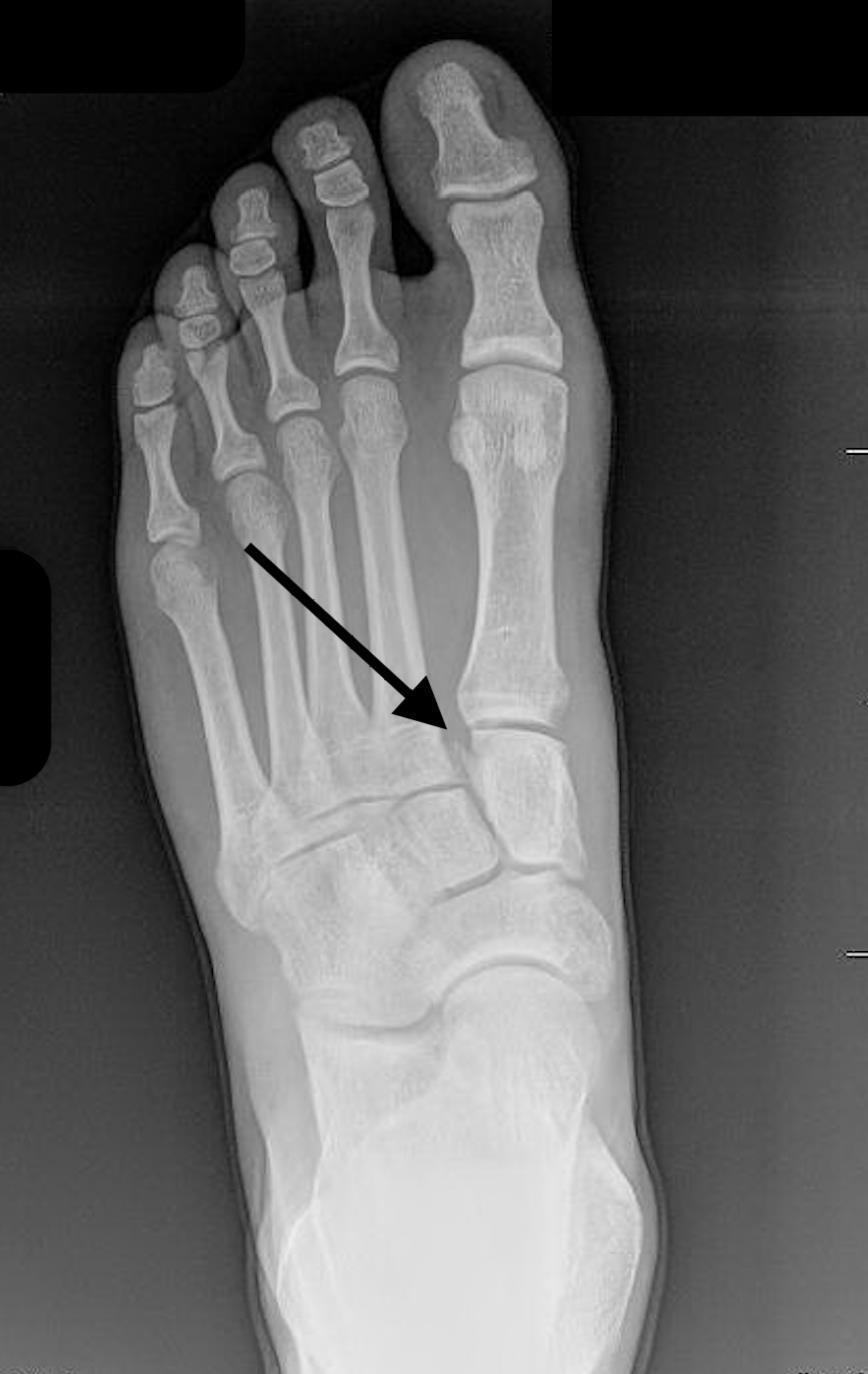

A

JONES

- Transverse fracture of the fifth metatarsal base, occurring at least 15 mm distal to the proximal end of the bone, distal to the insertion of the peroneus brevis